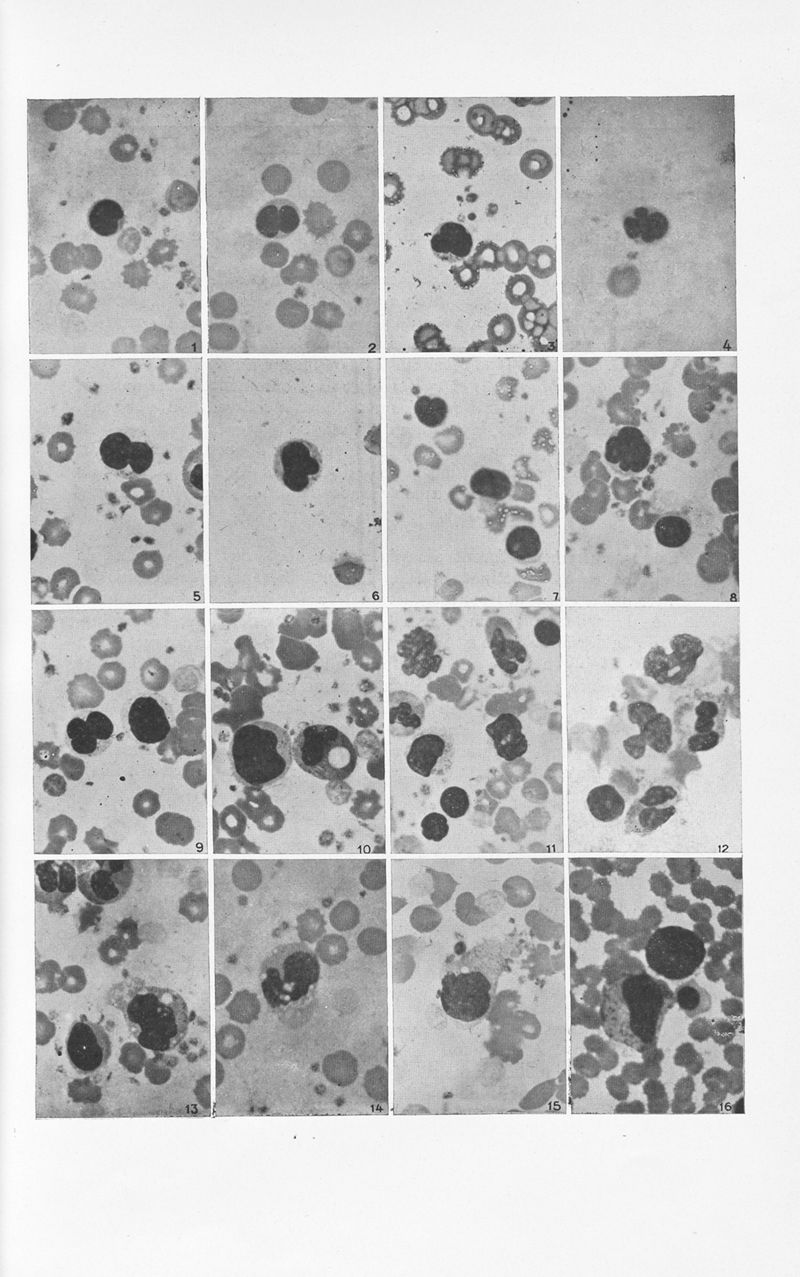

Annales de dermatologie et de syphiligraphie

7ème série, tome VIII. - Paris : Masson, 1937.